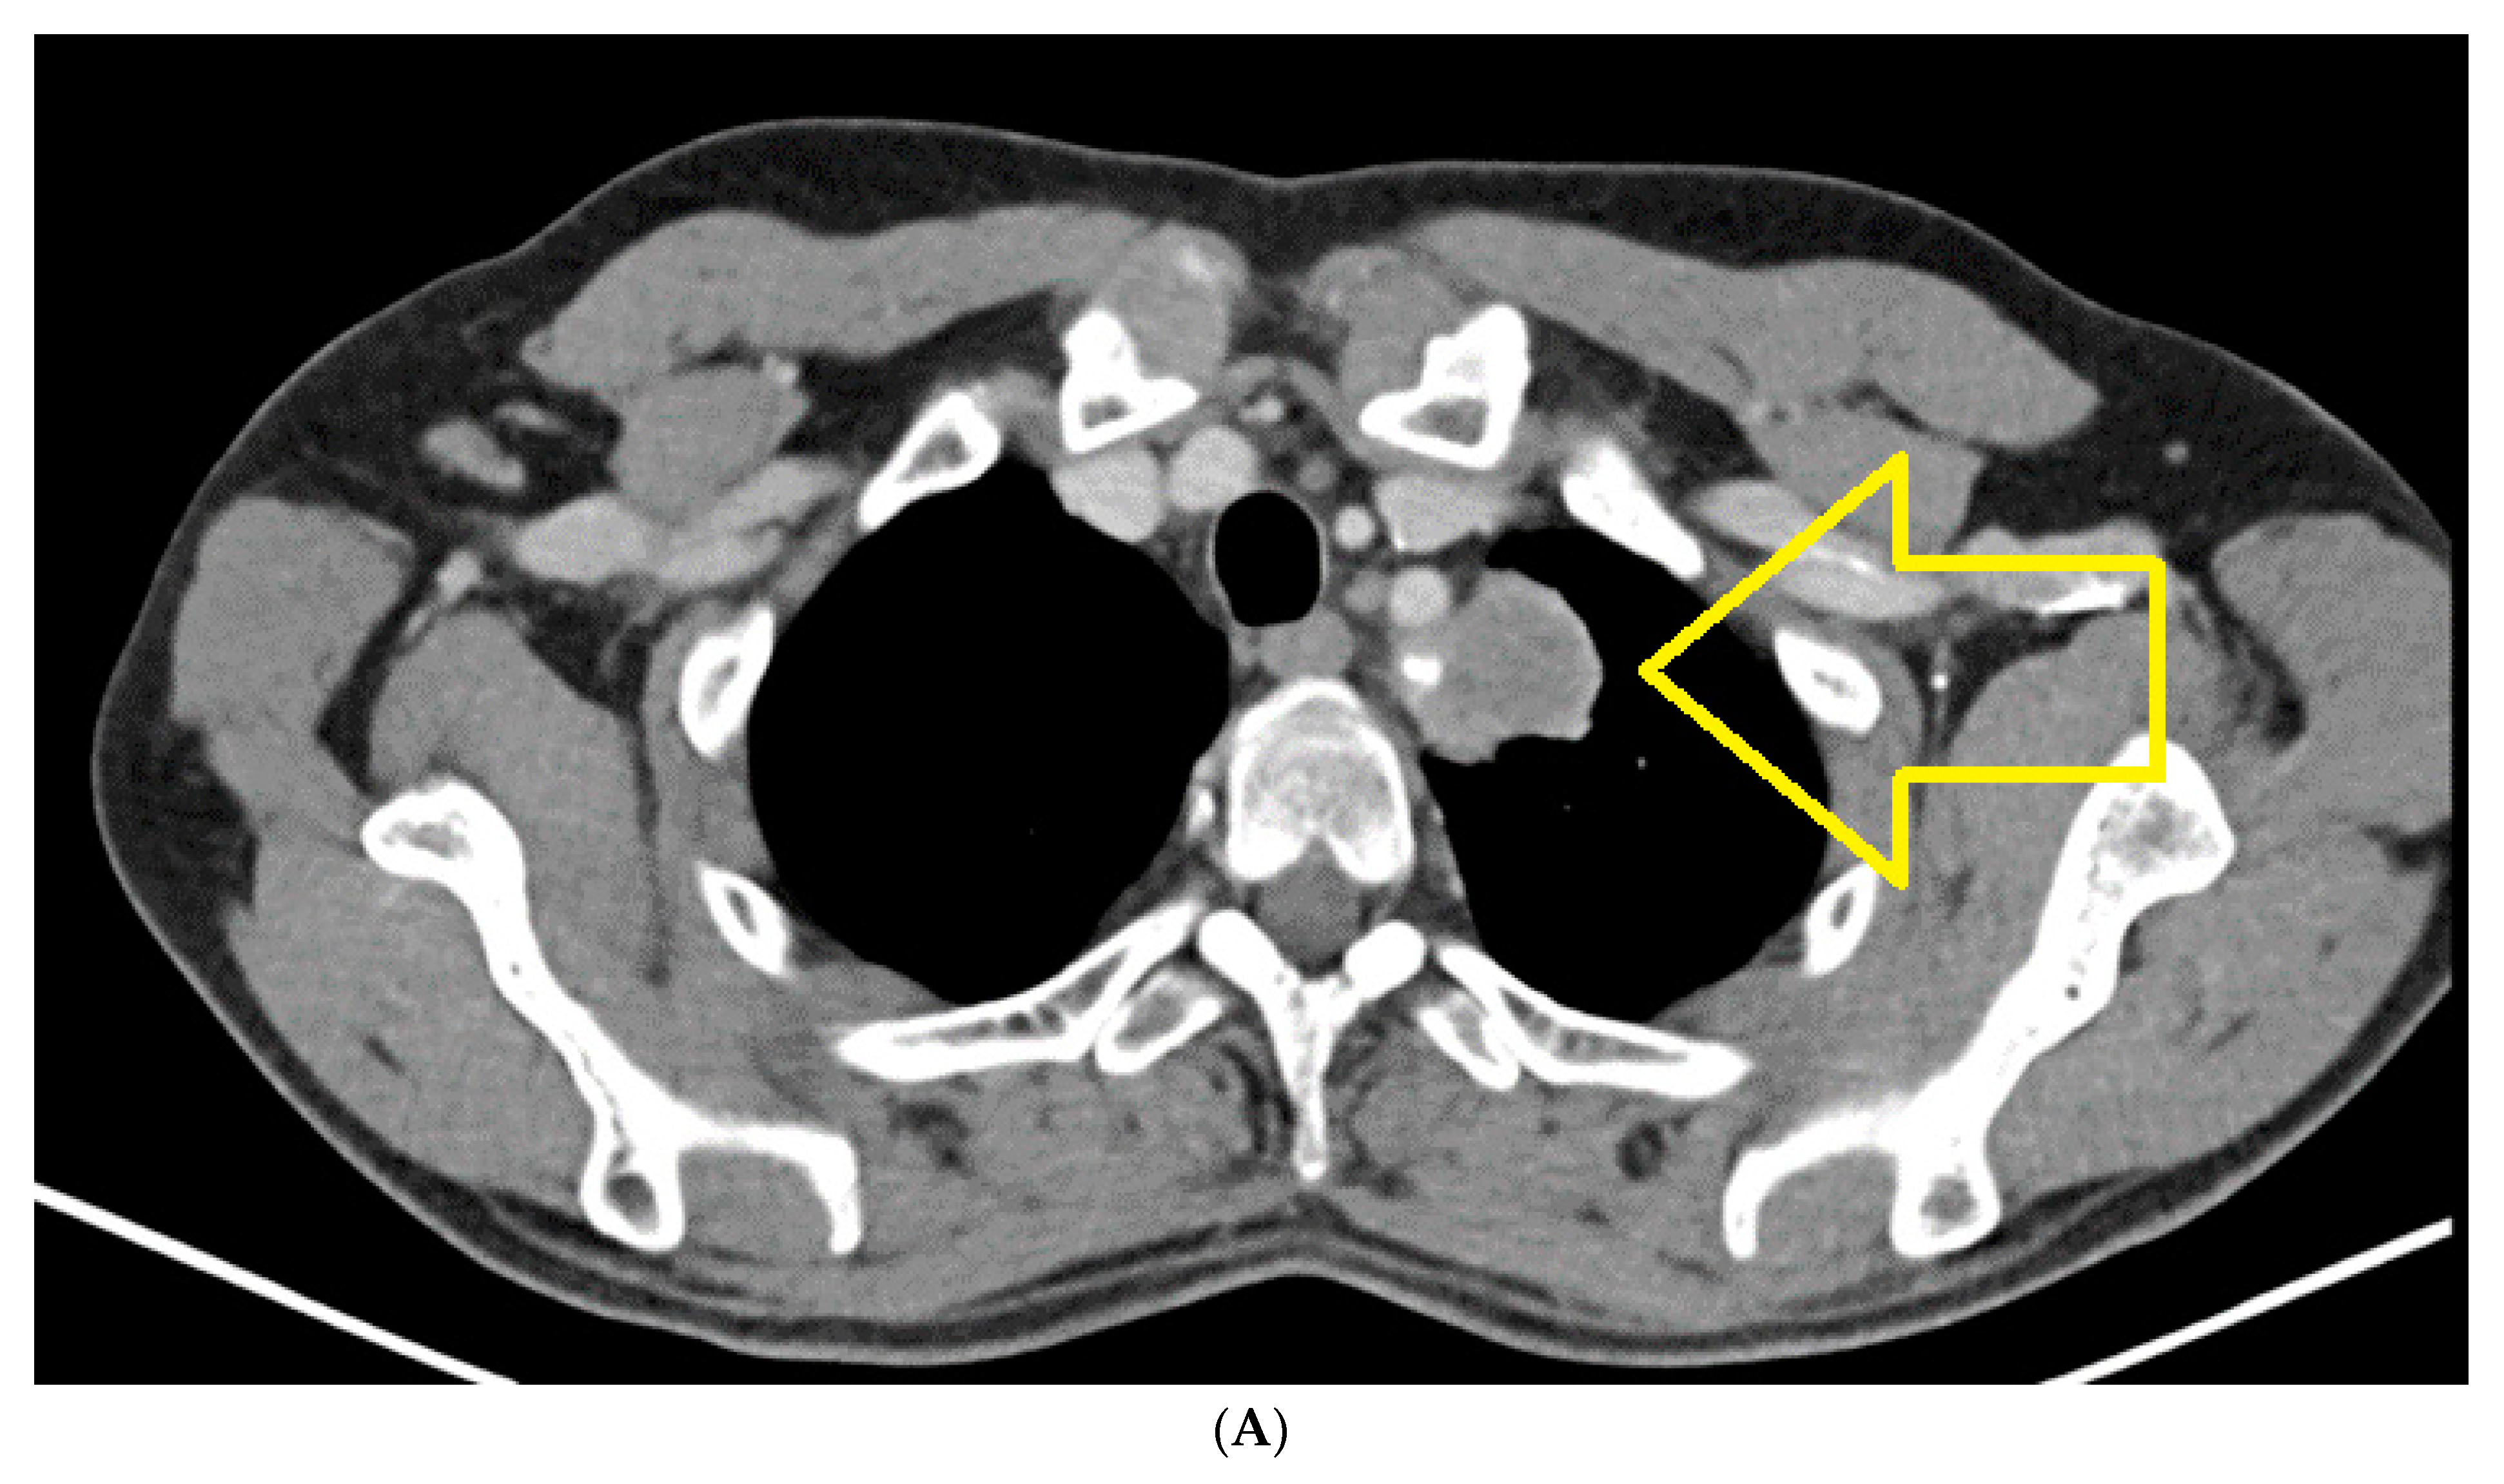

2. Case Report